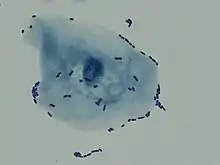

| Multiple white cells seen in the urine of a person with a urinary tract infection using microscopy | |